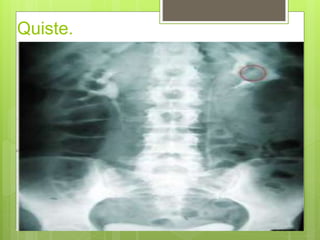

 Si se sabe por la radiografía simple que hay

una masa en una parte del riñón, ver si tiene la

misma opacidad que el resto del riñón o si

sigue inmodificada después de la inyección.

 El hecho de que no aumente la opacidad de la masa

sugiere que se trata de un quiste sin circulación

importante.

 Si aumenta de opacidad con el resto del riñón, lo

más probable es que sea un tumor.

Quiste.